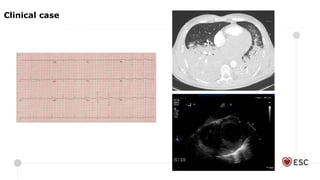

Clinical case

Clinical features

Loss of pulse pressure/pulsatile waveform

• absence of pulsatility in setting of appropriate support (60-80% of predicted CI) = inability of heart to overcome

increase in afterload despite decrease in preload and work

Pulmonary oedema +/- haemoptysis

Echocardiographic features:

Progressive ventricular dilatation

Worsening mitral regurgitation

Retrograde pulmonary vein systolic flow

Lack of aortic valve opening

Intraventricular stasis and thrombus formation

Inadequate LV decompression